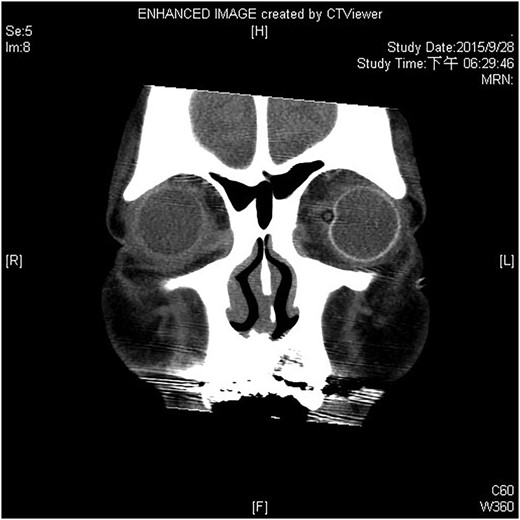

A 60-year-old man was admitted to our medical ward due to aspiration pneumonia. He had a medical history of diabetes mellitus, end-stage renal disease; a tuberculosis bacilli-related thoracic spine infection with paraplegia, and a previous coronary artery bypass graft. During his third day at the hospital, he obtained a ballpoint pen and inserted it into his left eye. On physical examination, the patient appeared to be alert with normal vital signs. The ballpoint pen protruded from his left upper eyelid; it was firmly lodged in his left medial orbit between the globe and nose, causing left eye proptosis (Fig. 1). Neurologic examinations revealed that the patient was neurologically intact except for complete left ophthalmoplegia. Brain CT scanning revealed a tubular foreign body that was located in the anteroposterior plane extending from the orbital apex and directly into the parasellar region (Fig. 2). The metallic portion of the foreign body was entrapped in left optic canal (Fig. 3). There was no evidence of intracranial hemorrhaging or a rupture in the globe (Fig. 4). The patient was treated with high-dose steroids to protect the optic nerve. The plastic ballpoint pen and metallic tip was withdrawn from the orbit smoothly at bedside, and no craniotomy was required. The ballpoint pen had been inserted to an estimated depth of 7 cm through the eyelid and into the orbit. The patient was then transferred to the ICU for close neuro-observation. We initiated intravenous broad-spectrum antimicrobials and vancomycin therapy and continued these medications for three weeks. A psychiatrist was consulted for a complete psychiatric evaluation and suicide prevention. The follow-up CT scan showed no retained foreign bodies or intracranial hemorrhaging (Fig. 5). At the last follow-up examination 2 months after the injury, the patient presented with complete left ophthalmoplegia and blepharoptosis but intact visual function.

The follow-up CT scan shows residual hematoma in the orbital cavity; no retained foreign bodies or intracranial hemorrhaging.